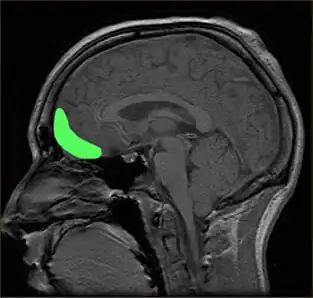

Approximate location of the OFC shown on a sagittal MRI